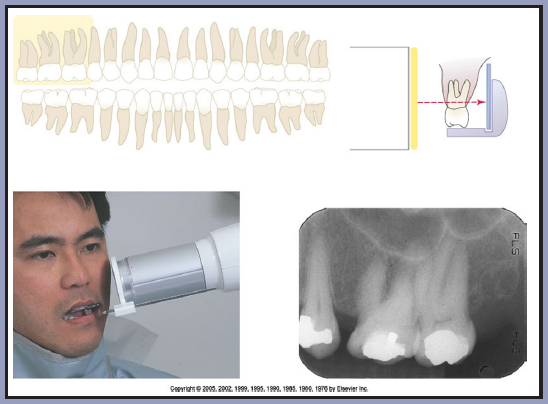

Bitewing images are parallel images because the receptor is positioned parallel to the long axis of the teeth and the beam is perpendicular to the receptor as in Figure 60. A bitewing tab is utilized to stabilize the receptor as the patient bites together.

Bitewing radiographic images are usually exposed with an indicated vertical angulation of +10 degrees (tube head points down for positive (+) angulation). This angulation provides an acceptable compromise for the differences between the long axis inclinations of the maxillary and mandibular teeth. Horizontal angulation is aligned with the direction of the contact, and the central ray is directed between the contacts of the teeth to be radiographed. Horizontal angulation is achieved when the central ray of the x-ray beam is directed specifically between the contacts of the teeth to be radiographed.

The interproximal examination may be done using a special type 3 bitewing receptor but is preferably achieved by using type 2 receptors fitted with a tab. (Figure 61) There are also receptor holding devices available that support the receptor as well as provide an external reference for positioning the tube head. The patient stabilizes the receptor by gently biting together on the manufactured tab or on the holding device.

Tube head position is illustrated in Figure 62, and a sample set of bitewing radiographic images are illustrated in Figure 63.